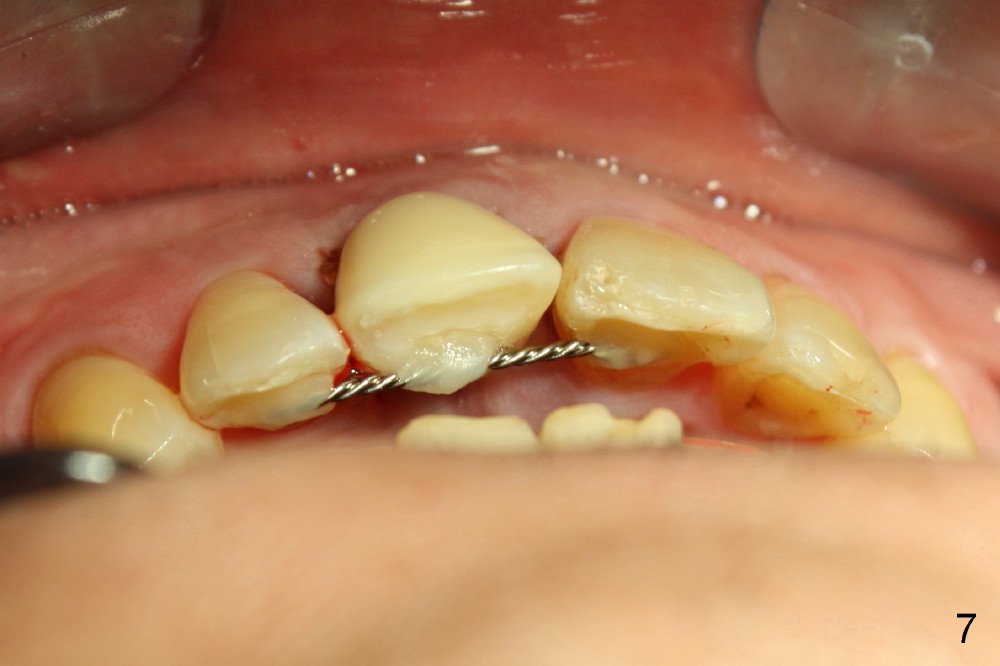

The provisional is dislodged 3.5 months postop; there is no labial atrophy (Fig.8 black arrowhead). The permanent crown (Fig.9 C) is harmonious with the papillae (*). When the try in crown is removed, the gingival tissue looks healthy (Fig.10 *).